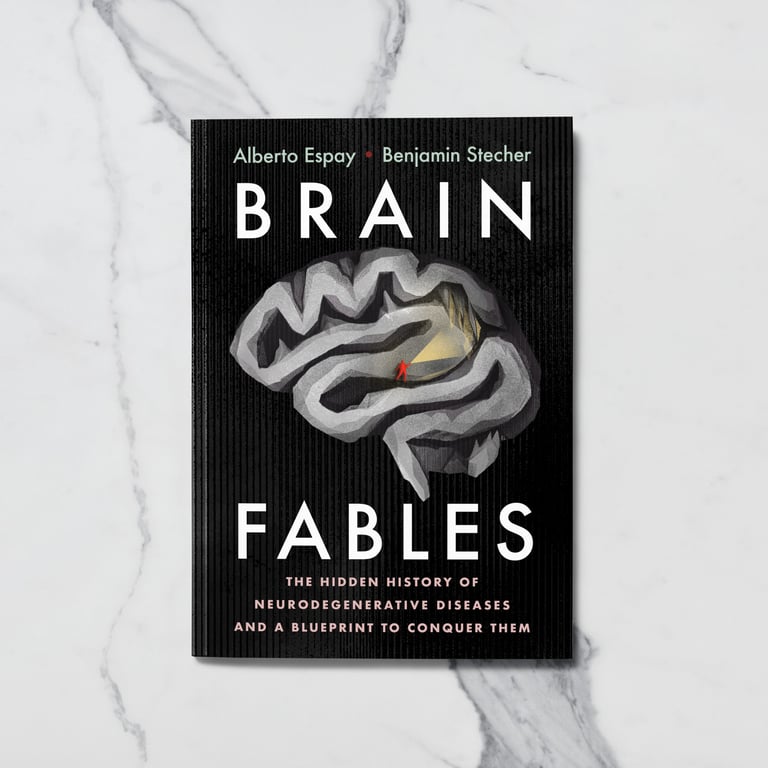

- Was this project commissioned?

Commissioned - Commissioner Name

Alberto Espay and Benjamin Stecher - Commissioner Company

Alberto Espay and Benjamin Stecher - Who was the work commissioned for?

Cambridge University Press - Agent

Salzman International - Agent Instagram

@salzmanart - Personal Website or Portfolio Link

luisajung.com - Instagram

@luisa.jung.works - Biography

Luisa Jung was born in Buenos Aires, she is both an illustrator and an architect. Her work spans from analogue collage to digital art. Her client portfolio includes renowned names such as the New York Times, Der Spiegel and Cambridge University Press. Luisa lives and works in Cologne, Germany. - Where are you currently based?